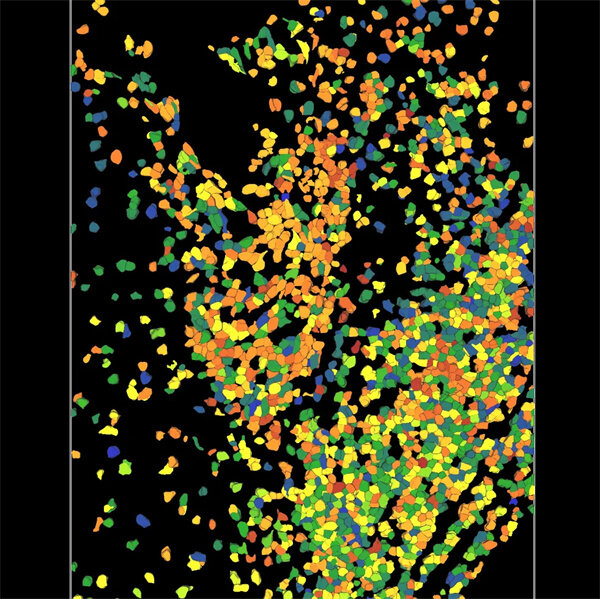

图片说明:3D人类扁桃体组织,使用8种OPAL染料和DAPI标记的9-plex人类扁桃体组织,在STELLARIS共聚焦系统上获取。使用Aivia中的3D Multiplexed Cell Analysis recipe对组织中的上皮细胞和免疫细胞进行了分割。

图片来源:Leica Microsystems的Dr. Tatjana Straka。

我们最前沿的deep learning模型,无需细胞核染色也可快速精准分割3D细胞。增强后的cellpose【1】模型增速78%,这将大幅加速您的研究进程,助您迅速获得空间组学洞察。更棒的是,您可以通过Aivia Community在任何PC工作站上无缝分享您的突破性发现,与全球科学家共同进步!